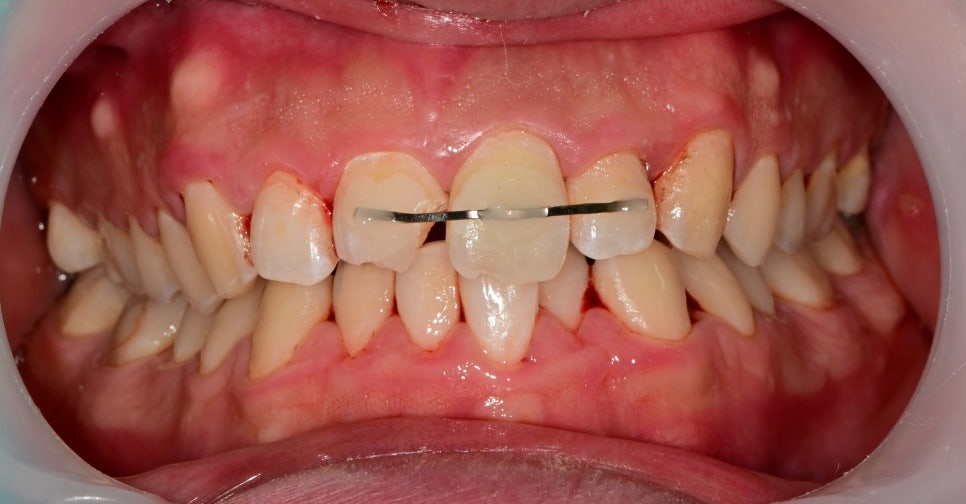

첫 번째 환자분과 다르게 이분은 치아의 동요도도 관찰되었기 때문에 사진처럼 치아를 고정할 수 있는 임시 치간 고정술을 진행했습니다.

흔들리는 치아는 정도에 따라 고정 장치의 유지 기간이 좀 다를 수 있지만 일반적으로 2~4주 이상은 권하고 있지 않습니다.

엑스레이 내에서 추가적인 치아 파절의 흔적은 보이지 않아 치아의 흔들림을 고정시킨 후 치아 파절 부위나 치아 신경의 생활력을 평가하기 위해 2주 후 체크를 해봤습니다.

2주 후 체크를 했습니다.

고정 장치를 제거하고 치료 중간에 사진이긴 합니다만

치아의 흔들림은 이제 잡혔지만

가운데 고정했던 치아의 색이 어둡게 변한 것을 볼 수 있습니다.

일반적으로 치아의 신경 즉, 치수 괴사가 일어나게 되면 치아가 어두워집니다.

이것은 이미 생활력을 잃었기 때문에 해당치아는 신경치료 후 크라운치료를 결정했습니다. 그 옆의 치아 또한 파절편에 컸고 주변 금이 가있는 치아파절편들이 많지만 신경의 생활력은 살아있어서 신경치료 없이 크라운치료로 마무리하기로 했습니다.